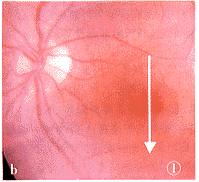

图1 a.黄斑区内界膜反光增强,黄斑区厚度增加,中心凹神经上皮层内可见小暗区(箭)。提示黄斑区水肿,视网膜前膜形成;b.可见黄斑区反光稍强,未见其它异常。图中箭示OCT扫描轴位 图2 a.黄斑区视网膜神经上皮层增厚,可见小暗区(双箭),鼻侧见玻璃体后界膜反光带并向黄斑延伸(单箭),提示黄斑水肿合并玻璃体后脱离;b.可见黄斑区反光稍强。图中箭示OCT扫描轴位 图3 a.黄斑区神经上皮层部分断裂(箭),其下可见部分视网膜组织,提示黄斑囊样破裂所致的板层裂孔;b.黄斑区可见黄白色漆样裂纹,中心凹可见一暗红色灶内有一黄白色小点。图中箭示OCT扫描轴位 图4 a.视网膜色素上层层连续性破坏(箭),提示黄斑视网膜色素上皮损伤;b.黄斑区可见少许黄白点状渗出,未见其它异常。图中箭示OCT扫描部位